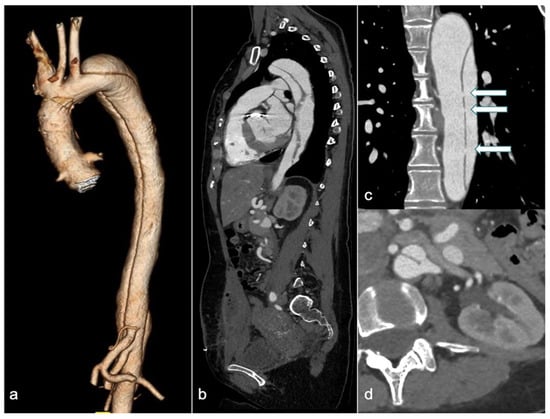

4.1. CTA: Challenges and Approaches in Clinical Practice

CTA is the first-line imaging modality for diagnosing suspected AD, due to its wide availability, high accuracy, short acquisition time, and ability to provide a comprehensive assessment of the thoracoabdominal aorta (Figure 3) [63].

Figure 3.

A 31-year-old woman with Marfan syndrome and a history of ascending aortic dissection, previously treated with a Bentall procedure, presented with chest pain a few days postpartum. CTA revealed an extension of the dissection into the descending thoracic and abdominal aorta (3D volume rendering in (a), and sagittal and coronal views in (b and c), respectively), with simultaneous enhancement of both the true and false lumens due to multiple intimal fenestrations (arrows in (c)). The sagittal view (b) shows a heterogeneous collection into the rectus abdominis muscles following a recent cesarean section. Axial image (d) reveals the left renal artery originating across both the true and false lumens. CTA: computed tomography angiography and 3D-VR: 3D volume rendering.

However, in pregnant patients, the primary concern is fetal radiation exposure, especially if the fetus is included in the primary radiation field to evaluate the abdominal extent of the AD. Advances in imaging acquisition and processing over the past decade have significantly reduced radiation doses. The effectiveness of ATCM systems and IR techniques in reducing the radiation dose has been well established [64]. In recent years, studies have also demonstrated the feasibility of low tube potential protocols for aortic CTA [65,66]. Fink et al. reported that whole-aortic CTA can be performed with both very low radiation and iodine doses, while maintaining diagnostic image quality, by employing a body mass index (BMI)-adapted protocol [67]. With the introduction and implementation of dual-source CT (DSCT) and DECT technology, the potential savings in radiation and iodine dose for aortic CTA have continuously increased. The use of a DSCT high-pitch protocol for dose reduction has been reported. This protocol decreases the scan time for the entire aorta to approximately 2 s, resulting in a very low radiation dose [68]. Apfaltrer et al. demonstrated that high-pitch CTA of the aorta results in a 45–50% reduction in radiation exposure, along with contrast medium savings, while maintaining vessel attenuation at a diagnostic level [69]. DECT, by comparing two different energy levels, distinguishes materials based on their effective atomic numbers. Virtual non-contrast (VNC) images have been used in AAS imaging protocols for the diagnosis of aortic intramural hematoma (IMH) by subtracting the iodine attenuation from contrast-enhanced scans [70]. This approach demonstrates excellent diagnostic performance while reducing the number of acquisitions and achieving a mean effective dose reduction of 40% [71]. Moreover, various institutions have established protocols to minimize radiation exposure through decision-making algorithms and careful interdisciplinary collaboration. Patel and colleagues designed a specific protocol for patients with suspected AAS who had no prior history of aortic disease and no abdominal or pelvic symptoms. This protocol involved an initial CTA of the chest, which was reviewed by a monitoring radiologist while the patient remained on the scanner table. If no aortic pathology was found, the examination was terminated; conversely, if pathology was detected, a CTA of the abdomen and pelvis was immediately performed. This approach reduced radiation exposure by up to 14.6% [72]. Such strategies are particularly useful for pregnant women, as they can help avoid including the fetus in the primary radiation field whenever possible. Further research is required.